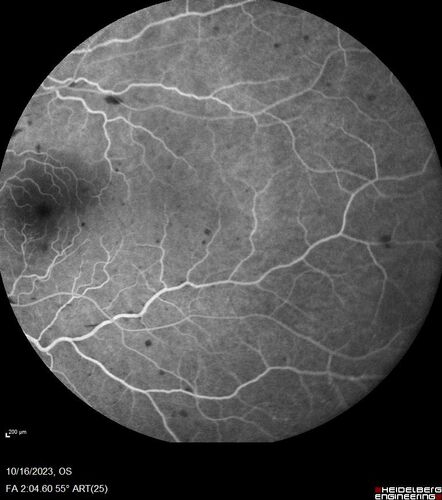

Central Retinal Vein Occlusion with cilioretinal artery occlusion

63 year old female who lost vision in the left eye 2 days ago. She was in the emergency room and had a lot of tests done which were all reportedly normal. The right eye is OK.

VA OD: Dcc20/25 NccJ2

VA OS: Dcc20/200-1 PHNI Ncc20/400-1

IOP: TP: OD:11 OS:12